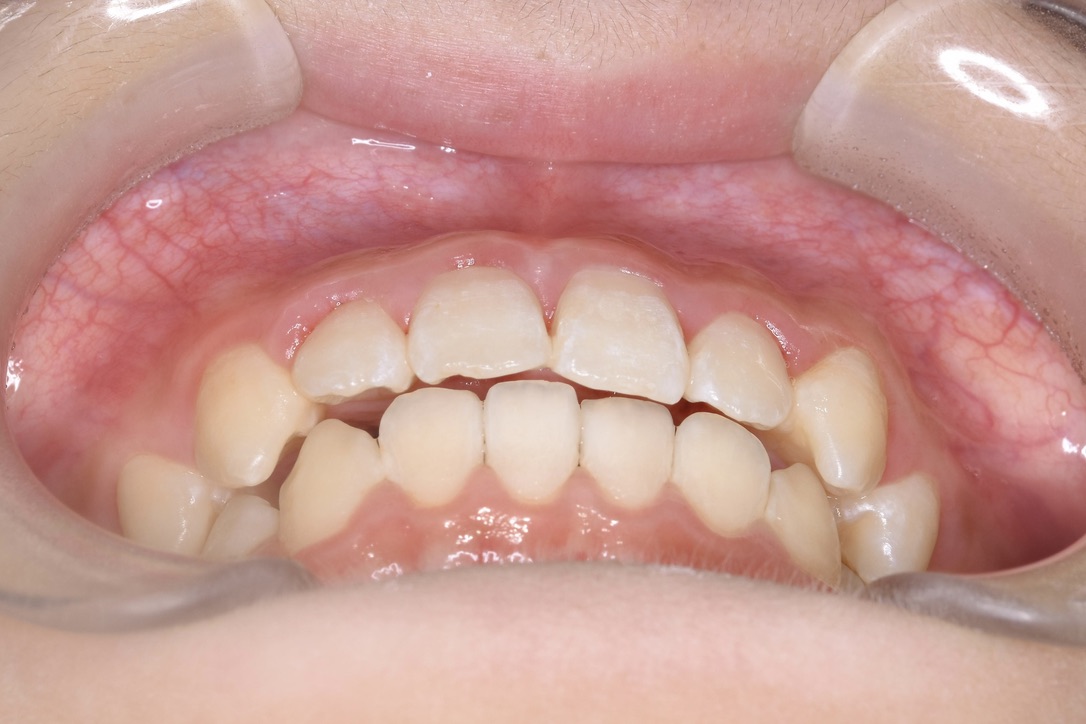

AFTER

主訴 通っている歯医者で矯正した方がいいと言われて気になっている。下の前歯がでこぼこしている。

診断名・主な症状 下顎前歯の叢生を伴う過蓋咬合

年齢 7歳

治療内容 上下の歯並びの幅を拡げつつ、前歯の関係を改善しました。

使用装置 急速拡大装置

リンガルアーチ

機能的矯正装置(マイオブレース)

抜歯部位 抜歯なし

治療期間 2年 + 後戻り止め期間(3年 )

通院回数 20回

費用 50万円程度(税別)  29331

リスク・副作用 痛み、歯肉退縮、歯根吸収、抜歯に伴う出血や腫れが生じることがあります。